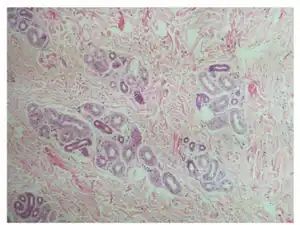

| Histology-Prominent increase in eccrine coils and dermal fibrosis | |

An eccrine nevus is an extremely rare cutaneous condition that, histologically, is characterized by an increase in size or number of eccrine secretory coils.[1]:โ774โ